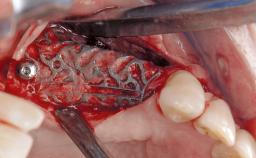

Resective Surgical Treatment of Peri-Implantitis Including Implantoplasty

In this case, Myroslav Solonko, Ignacio Sanz Sánchez and Mariano Sanz present a treatment that aims to eliminate exposed implant threads by modifying the implant surface, converting a moderately-rough surface into a smooth surface.

A 63-year-old male patient was referred to the post-graduate periodontal clinic of the Complutense University of Madrid for the treatment of peri-implantitis. According to the patient’s record, all his maxillary teeth had been extracted ten years previously due to severe periodontitis, and a full-mouth implant-supported restoration on eight implants was placed. No supportive periodontal therapy was provided apart from occasional check-ups by the restorative dentist.